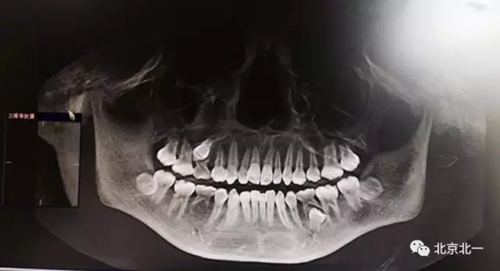

圖一:拔牙前影像片(CBCT)